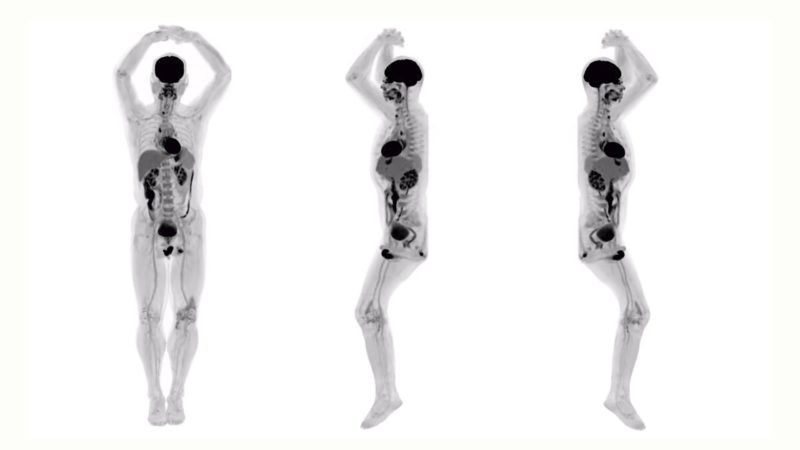

A kaliforniai UC Davis kutatói a sanghaji United Imaging Healthcare szakembereivel közösen hozták létre az EXPLORER nevű testszkennert, amely a röntgensugarakat alkalmazó komputertomográfiát (CT) és a pozitronemissziós tomográfiát (PET) kombinálja. Ez hétköznapi nyelvre lefordítva annyit jelent, hogy a gép egyetlen szkenneléssel képes háromdimenziós képet alkotni a teljes emberi testről.

„Elképesztő az a részletesség, amire képes az eszköz – írta Ramsey Badawi, a UC Davis nukleáris medicina osztályának vezetője az egyetem közleményében. – Olyan apróságokat is láthatunk a felvételeken, amelyekre az eddig használt PET-szkennerek nem képesek. Az külön lenyűgöző, ahogy a videókon látható a röntgenvizsgálathoz használt kontrasztanyag mozgása is, három dimenzióban. Jelenleg erre egyetlen hasonló eszköz sem képes.”

Az EXPLORER az elképesztő felbontású felvételeket ráadásul rendkívüli gyorsasággal készíti el: egy teljes testes felvételhez mindössze 20-30 másodpercre van szüksége, ami gyakorlatilag azt jelenti, hogy negyvenszer gyorsabb a jelenleg használt képalkotó berendezéseknél. Ez gyorsabb vizsgálatokat és alacsonyabb sugárterhelést jelent a páciensek számára. A jelenlegi PET-rendszerek csak sávokban képesek letapogatni az emberi test részleteit, így egy teljes vizsgálathoz akár 30-40 percre is szükség lehet, hogy egy nagyobb térbeli kép jöhessen létre. Ez azonban korlátozza az orvosok lehetőségeit, akik eddig nem tudták valós időben megnézni például a már említett kontrasztanyag mozgását.

Ezek a képek forradalmasíthatják az orvoslást (Fotó: UC Davis)